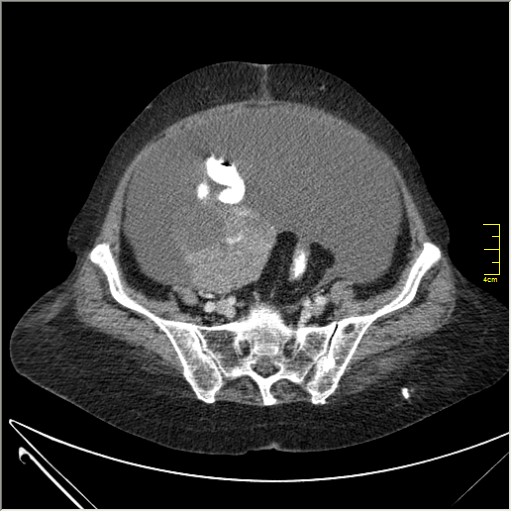

Женщина 72 года. Поступила с жалобами на вздутие живота. После осмотра хирургом, была сразу направлена на КТ брюшной полости.

Итак, асцит с объёмным образованием таза. В данном случае можно быть более конкретным, у пациентки неоплазия правого яичника с региональной лимфаденопатией (увидели?) и выраженным асцитом, характерным именно для злокачественных опухолей яичников. Пациентка оперирована ( операция Вертгейма); диагноз верифицирован: аденокарцинома правого яичника (серозная). Направлена к онкологу для дальнейшего лечения.